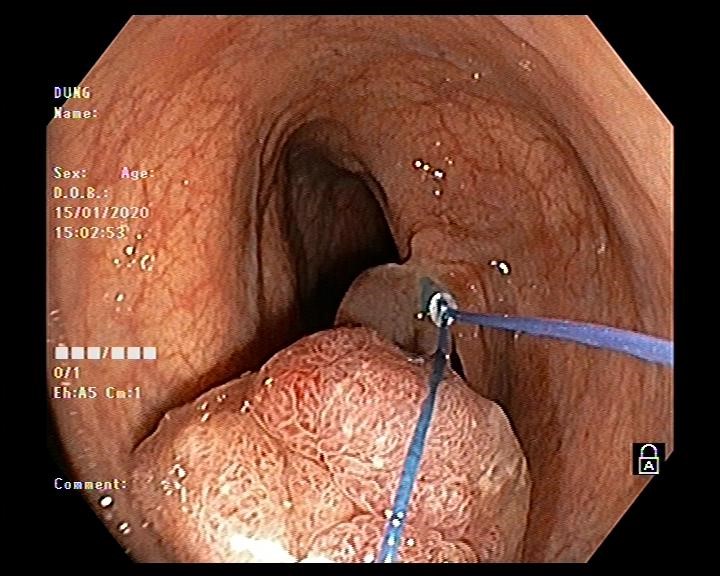

Hình ảnh nội soi đại tràng cắt polyp

Vấn đề đặt ra là với kích thước và tính chất polyp như vậy thì có khả năng polyp được nuôi bằng mạch máu lớn, nếu chỉ cắt đốt bằng phương pháp thông thường thì nguy cơ xuất huyết ồ ạt sẽ rất cao. Do đó bác sĩ nội soi Ths Vũ Thanh Tùng quyết định sử dụng vòng Endoloop để thắt cuống polyp trước khi tiến hành cắt đốt. Thủ thuật diễn ra thuận lợi, nhanh gọn trong vòng 10-15 phút và không xảy ra tai biến dù là polyp này được nuôi bằng mạch máu lớn.

Hình ảnh thắt cuống polyp bằng vòng Endoloop